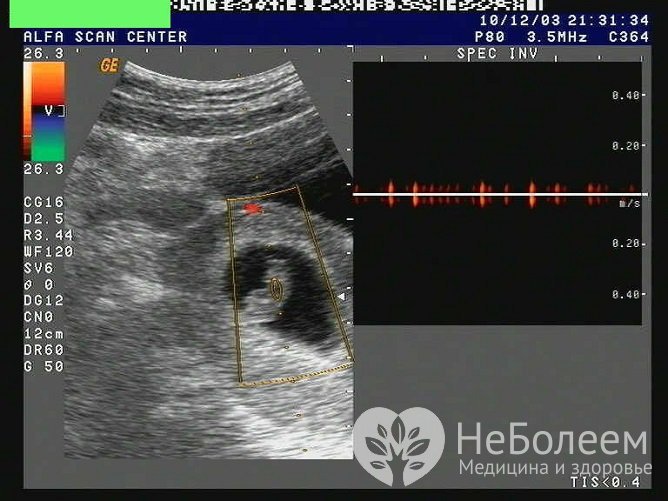

Источник: astrakhan-pek.ruИз методов инструментальной диагностики используется УЗИ органов малого таза. В ходе исследования обнаруживается, что признаки жизнедеятельности плода (сердцебиение, двигательная активность) отсутствуют. При анэмбрионии эмбрион отсутствует в плодном яйце после 7-й недели беременности, размер плодного яйца при этом не соответствует норме предполагаемого гестационного возраста.

В ряде случаев размер плодного яйца соответствует норме, однако визуализируется эмбрион меньших размеров без сердцебиения. В случае недавней гибели плода видны плодное яйцо и плод без признаков жизнедеятельности. При более продолжительном пребывании погибшего плода в полости матки его визуализация невозможна, структура плодного яйца резко изменяется (определяется деформация, нечеткие форма и контуры плодного яйца, множественные перетяжки и пр.). К признакам гибели плода на более поздних сроках относятся выраженное маловодие и повреждение костей черепа плода со смещением костных отломков и захождением одного отломка за другой.